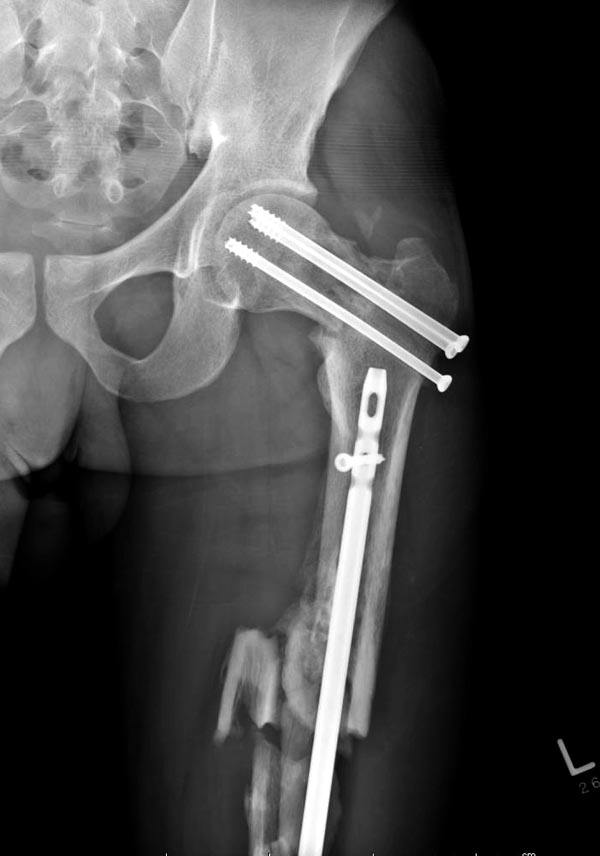

Здесь выставлен ренгенограммы больного, ему 21, травму получил в результате высокоскоростной погони на украденной машине, которая закончилась смертью трех остальных “боевых комрадов”. Начатую коллегой открытую операцию на шейке пришлось закончить мне, установкой винтов и ретроградной фиксацией бедра. Выписка в обычное сроки и наблюдался амбулаторно. Каждый раз напоминали о возможности осложнений ввиде несращения! По истечению 4 месяцев появились признаки варусной деформации. На СТ срезах несращение шейки и бедра. Риминг, замена на более толстый гвоздь и вальгусная остеотомия.

Сразу скажу, что пациент вчера (8.04) прооперирован - артротомия, остеосинтез мыщелков большеберцовой кости канюлированными винтами, открытая репозиция отломков бедренной кости, ретроградный БИОС, остеосинтез надколенника (центральных его отломков) спицами с проволочной петлей. Двухкратная попытка закрытой репозиции шейки на операционном столе после синтеза бедра - абсолютно неэффективна. Учитывая продолжительность и травматичность операции, шейка отложена на 2-й этап. Плечо наверное на 3-й (если вообще делать). Снимки постараюсь предоставить, но чуть позже.